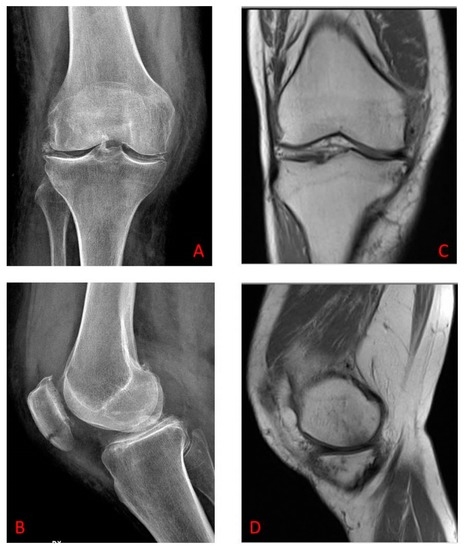

This study was performed in the “Polyclinic G.B. Morgagni” Mediterranean Foundation, Orthopedics Traumatology and Rehabilitation Unit in association with Physiocare—Center of Physical Medicine and Rehabilitation and our Biomechanics Research Laboratory. We included 66 patients, 35 males and 31 females, presenting pain and functional impairment with knee OA (PF and TF knee compartments), without concomitant chronic conditions. Patients were of a similar height and weight, had a median age of 63 (54–72 years) and a duration of disease of 5.5 (±4.32) years. The pre-treatment examinations included a complete medical history, physical examination with particular attention to the vital symptom of OA represented by the pain threshold and X-ray and magnetic resonance imaging (MRI) (Figure 1). According to the Kellgren and Lawrence grading scale [23], patients had Grade II or Grade III OA of the knee. We excluded those with allergic reaction to tape or any skin problem, the presence of any inflammatory arthritis, history of any injection at the knee, surgical intervention in this part within the last six months, suspicion regarding other pathologies in the knee, severe obesity, OA Grade IV, the full instability of the knee joint, trauma to the knee during the study or when patients failed to follow the treatment instructions. The most common symptoms presented at the initial phase of the OA disease and before the treatment were: pain, stiffness, swelling and cracking.

Figure 1.

(A,B) In the X-ray, there are radiographically-visible changes, such as narrowed joint space and thickening of the articular cartilage, Kellgren and Lawrence grade II/III. (A) X-ray anteroposterior projection in osteoarthritic knee from osteoarthritis (OA) patient; (B) X-ray lateral projection in osteoarthritic knee from OA patient. (C,D) In the MRI (magnetic resonance imaging), the signal intensity of the menisci is altered; the articular cartilage and the subchondral bone are also altered with increased bone density, KL Grade II/III. (C) MRI coronal view in osteoarthritic knee from OA patient; (D) MRI lateral view in osteoarthritic knee from OA patient.